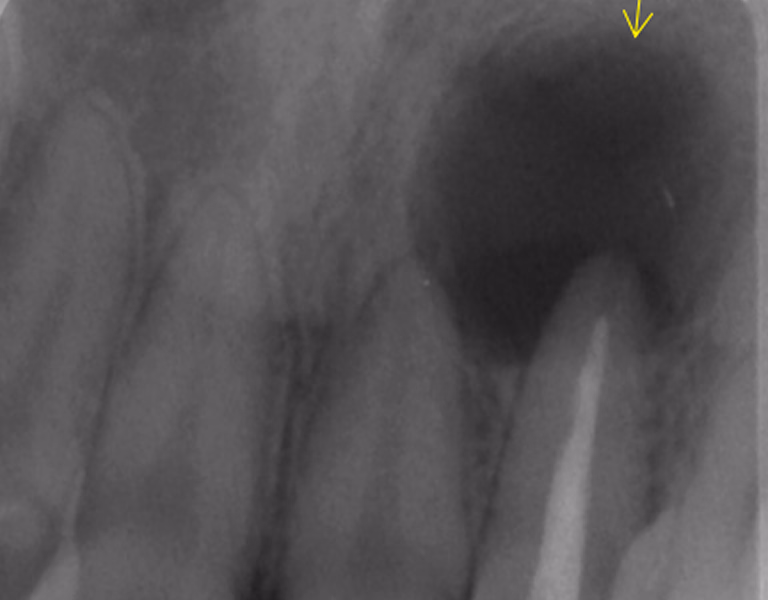

通常の根管治療では消失しなかった大きな根尖病変に対し外科的処置を追加。

1年後には病変の消失と症状の改善が確認できました。

今後も定期チェックで長期安定を図ります。